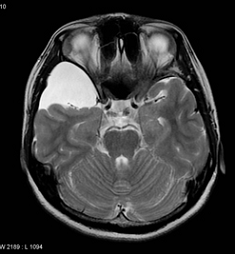

Doktorunuz semptom ve bulguları değerlendirdiğinde hidrosefaliden şüphelenirse tanıyı koymadan önce ayrıntılı bir şekilde hastalığın gidişatını öğrenmeli, ayrıntılı bir fiziksel ve nörolojik inceleme yapmalı, CT veya MRG ile görüntüleme yapmalıdır. Tetkikler sonucunda hidrosefali teşhisi konursa hasta daha ileri tetkik ve tedavi için beyin cerrahi uzmanına refere edilmeli.